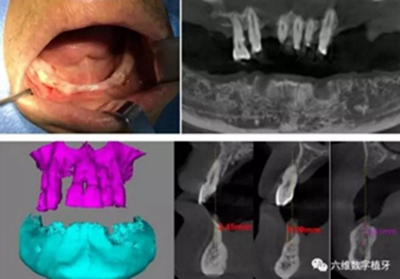

患者男,喜歡抽煙喝茶,有重度牙周病,下頜的牙齒已經(jīng)完全拔除,上頜牙齒在CT中可見,牙槽骨吸收很嚴(yán)重,牙根部分暴露,粘膜萎縮。要求:進(jìn)行下半口固定義齒即刻修復(fù)。

臨床檢查

從CT可以看出患者前牙區(qū)牙槽骨非常薄,有的地方3.5mm不到,左側(cè)4號(hào)牙位有嚴(yán)重的骨吸收,需要進(jìn)行植骨,后牙區(qū)離神經(jīng)管較近,設(shè)計(jì)種植短粗型種植體。